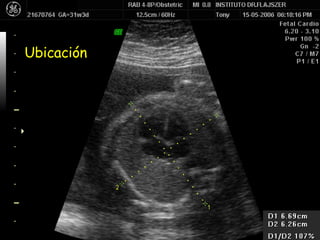

Ubicación

Tamaños